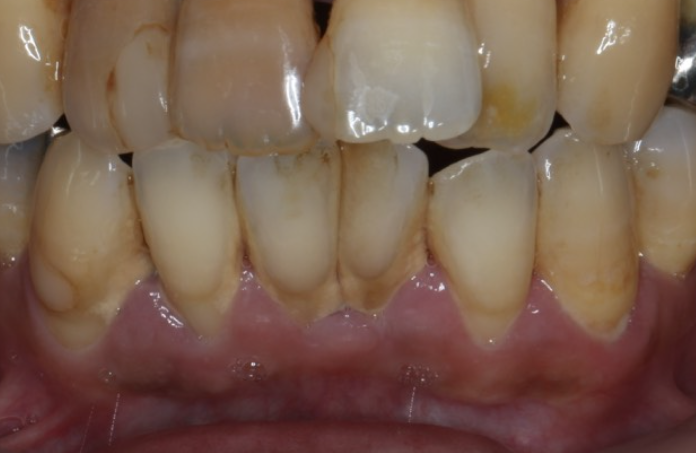

| 患者様データ | 40代 男性 |

| 来院時の主訴 | 「前歯を歯磨きすると痛いし、出血する。」 |

| 医院の診断 | 右上中切歯根尖性歯周炎、歯周病 |

| 通院期間 |

6か月 |

| 来院回数 | 10回 |

| 治療費 | 総額:歯周病治療に関しては保険適用診療。その他:370,000円(税抜) 【内訳】 歯周病治療(歯周病検査・歯磨きや生活習慣指導・歯石取りクリーニング) その他、精密根管治療 70,000円、ファイバーポストコア 20,000円、セラミック治療 140,000円×2 |

| リスクと副作用 | メインテナンスが必要、正しい歯磨き習慣が必要不可欠 |

| ここがこだわりのポイント!☝ | こちらは中等度の歯周病と虫歯を併発されていた患者様です。日々の歯磨き習慣を見直していただき、正しいブラッシング法を身につけたことで健康な歯肉を取り戻しました!短期間での治療を希望されていたので審美的な歯肉ラインの獲得はできませんでしたが、健康的な歯肉を獲得できました。 |